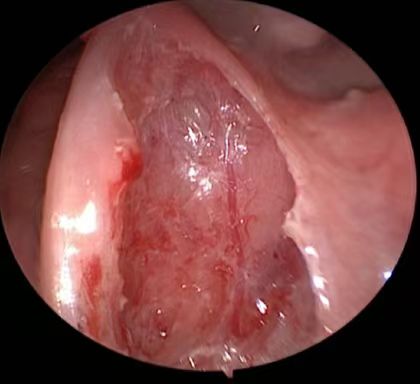

改良等离子扁桃体被膜血管保护技术

湖南省人民医院耳鼻咽喉头颈外科三病区周建波主任医师介绍,儿童阻塞性睡眠呼吸暂停低通气综合征多由于扁桃体、腺样体肥大所致,多指睡眠状态下频繁出现呼吸暂停、睡眠中断、低通气等所致的一系列病理生理变化,需手术治疗。目前,湖南省人民医院耳鼻咽喉头颈外科三病区不仅低温等离子射频消融术非常成熟,近年来通过不断探索,创新性地提出在等离子扁桃体手术中被膜血管保护技术,可以大大降低患儿手术创伤和术后痛苦,术后正常进食时间也大大缩短,术后康复过程明细加速,术后出血的概率远低于常规等离子手术,深受广大患儿及家长的欢迎。

周建波教授指出,常规等离子切除创面,其伪膜厚、疼痛明显,相对于成人,儿童疼痛耐受性差,有些患儿手术后切口疼痛拒绝进食,不愿吞咽、漱口,口腔卫生保持差,导致出现感染,从而使切口延迟愈合甚至出血等并发症的发生。而低温等离子消融术结合扁桃体被膜血管保护技术,其创面伪膜淡、疼痛轻微,明显加速了术后康复过程。(耳鼻咽喉头颈外科三病区   肖莉)